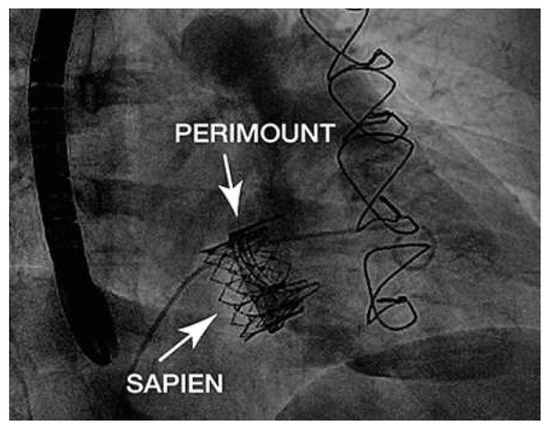

A 41-year-old women with Ebstein’s anomaly required tricuspid valve replacement six years ago. At that time a biological prosthesis was implanted. The tricuspid valve prosthesis became severely stenotic within five years. Instead of re-do surgery, th...